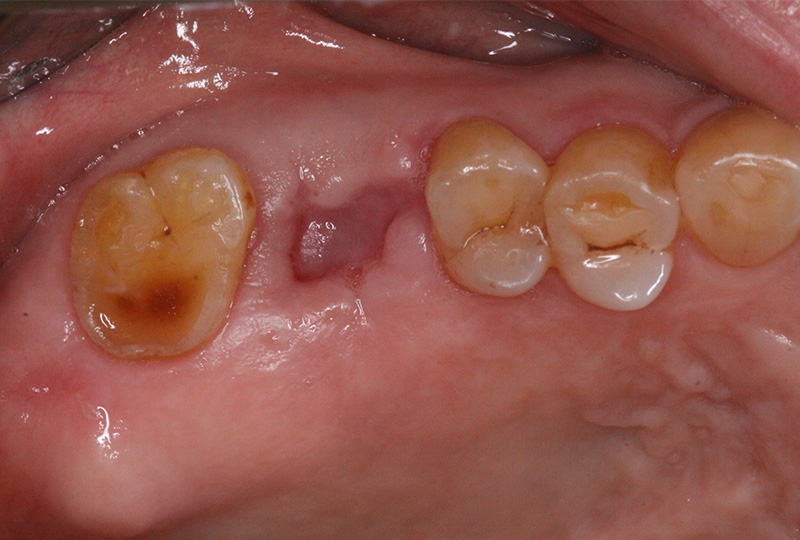

審美性にこだわった治療から保存が難しいと言われた歯の保存やお口全体をより良い状態にする一歩進んだ専門的な治療を行います。

『歯のひび(歯根破折)』など通常であれば抜歯と言われるような歯の保存や歯を失った所に親知らずなどを移動させる『歯の移植』など一般の歯科医院では行わない特殊な治療も行なっております。